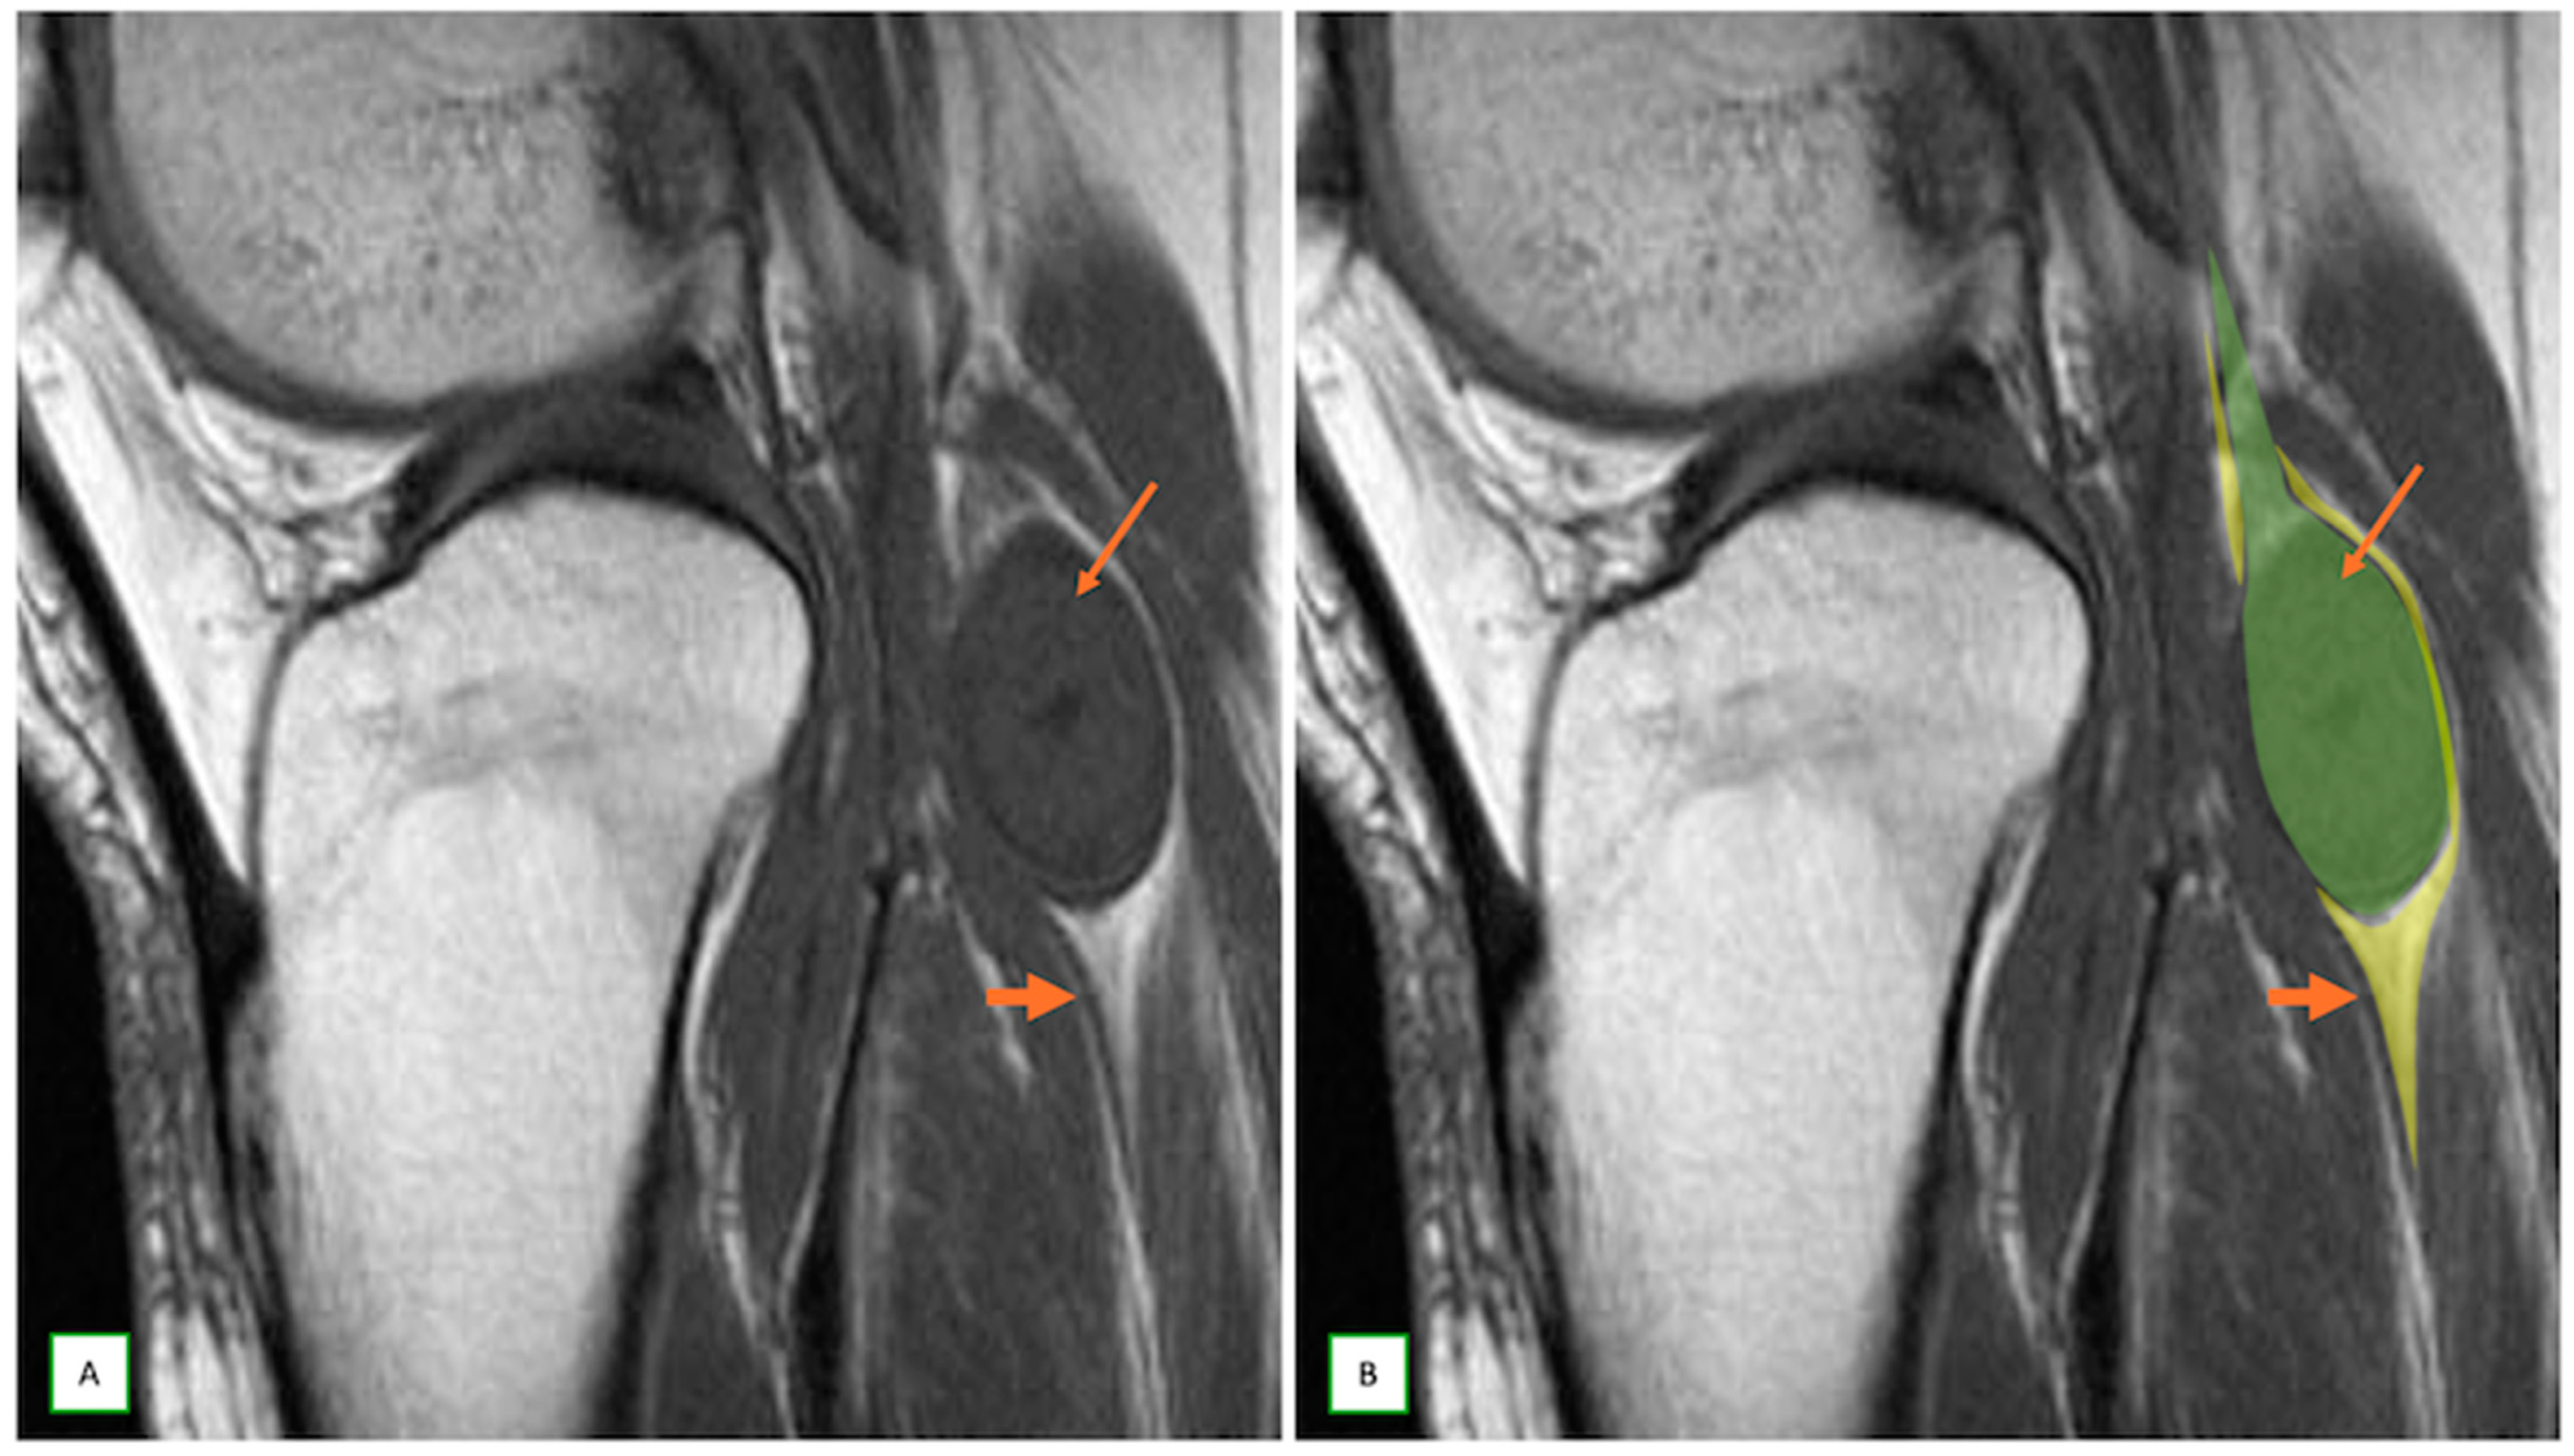

- Intraneural ganglion cysts usually occur near joints; are particularly common in the common peroneal nerve at the knee, owing to the intraarticular branch of the proximal tibiofibular joint; and appear as tubular, multiloculated cystic lesions following the course of the nerve on MRI [60,61] (Figure 16).

- Spinner, R.J.; Hébert-Blouin, M.-N.; Rock, M.G.; Amrami, K.K. Extreme intraneural ganglion cysts. J. Neurosurg. 2011, 114, 217–224. [Google Scholar] [CrossRef]

- Lisovski, V.; Minderis, M. Intraneural ganglion cyst: A case report and a review of the literature. Acta Med. Litu. 2019, 26, 147–151. [Google Scholar] [CrossRef]